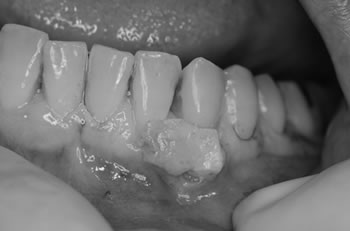

■術中

エムドゲインを塗布し歯肉移植(結合組織をもちいた根面被覆)をおこないました。